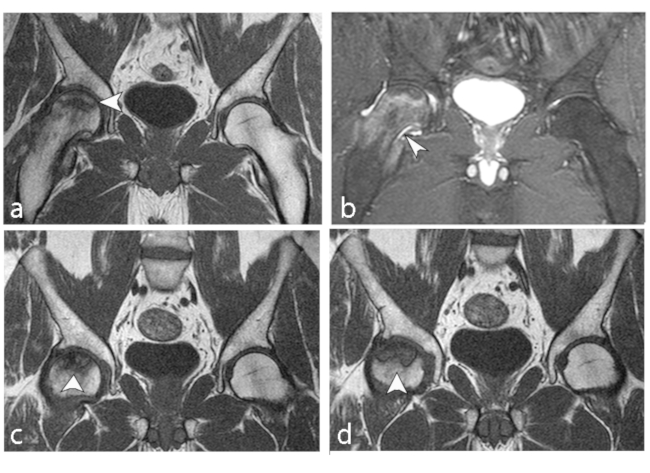

Existen varias escalas para determinar el grado de severidad de la ON de cadera mediante hallazgos imagenológicos con el fin de identificar y guiar el tratamiento adecuado, siendo las clasificaciones de Fitcat y Arlet, y/o Steinberg (►Tablas 2 y 3) las más utilizadas por los radiólogos al evaluar la progresión, desde la enfermedad radiológicamente negativa hasta el colapso de la cabeza femoral con desarrollo secundario de osteoartritis (►Figs. 2 y 3).6 Es de conocimiento que la importancia clínica de la ON depende casi por completo de la probabilidad de colapso articular, por lo que el volumen de la cabeza femoral afectada sería su predictor más relevante.

En RM en secuencia ponderada en T1, la intensidad de señal de la grasa de la médula ósea del cóndilo femoral afectado es reemplazada por un área con baja señal, asociada a una periferia de aún más baja señal (►Figs. 4 y 5).8 En la secuencia ponderada en T2 se visualiza lesión central hipointensa con área de señal alta periférica en relación al patrón de edema de la médula ósea (►Fig. 6).11

Tiene un buen pronóstico cuando el segmento que se afecta es pequeño o el tratamiento es adecuado (descarga completa de la pierna afectada asociado a analgésicos). En caso contrario, evoluciona a una artrosis grave de rodilla con dolor mecánico invalidante. El hallazgo que más influye en la evolución, es el volumen de la zona condílea de carga que se ha afectado, siendo un pronóstico desfavorable al afectarse >50% del tamaño con tendencia al colapso óseo y artrosis secundaria.5,11